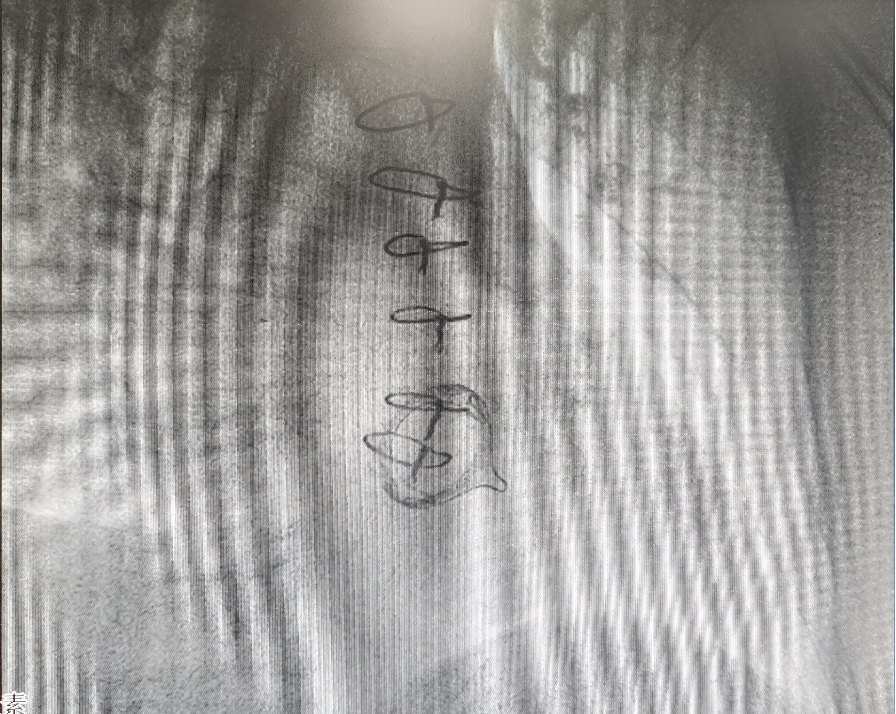

手术过程中,在数字减影血管造影的引导下,昃峰教授和蔡主任团队密切配合,通过精准操作,将仅2克重的Aveir起搏器顺利送达右心室理想位置,并设置理想参数。手术顺利完成。在起搏器的保护下,抗心律失常药物的使用使者的快速房颤得到有效控制。术后患者恢复令人欣喜。陈阿姨不仅很快可以下床活动,“再也不用提心吊胆地生活了!”患者质朴的话语道出了最真实的感受。